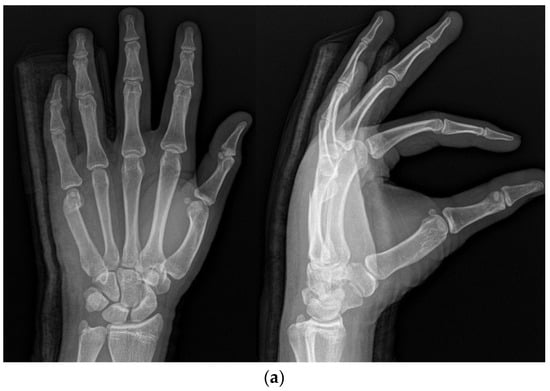

The IP method involved the insertion of an intramedullary nail in the anterograde direction. The entry point was selected at the base of the ulnar dorsal border of the metacarpal using a needle under imaging guidance. A small hole was made with a drill, into which the operator inserted the nail. The fracture was reduced via maneuver, and the nail passed across the fracture part (Figure 2a,b).

(a) Radiograph of a 16-year-old male patient with displaced little-finger metacarpal neck fracture. (b) Radiograph of a 16-year-old male patient who underwent the IP method using one intramedullary nail in the anterograde direction.